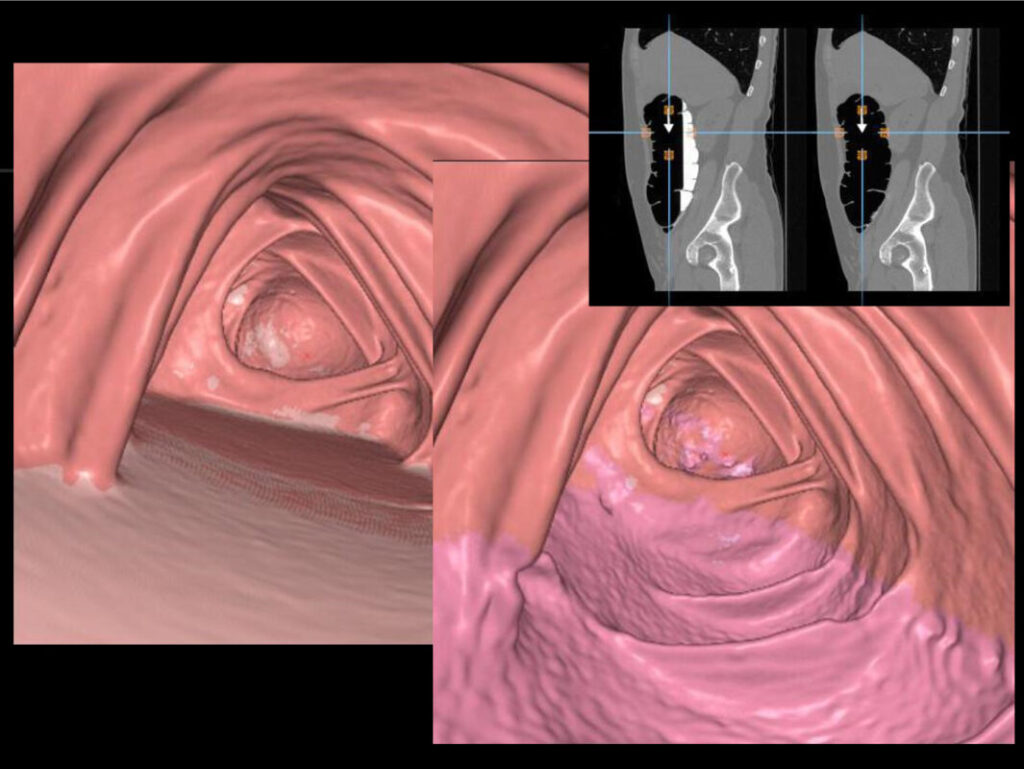

MSCT virtualna kolonoskopija ili MSCT ili CT kolonografija dijagnostička je metoda kojom se pomoću 2D i 3D slika debelog crijeva analizira cijelo debelo crijevo te organi abdomena i zdjelice. Smatra se neinvazivnom alternativom klasičnoj kolonoskopiji i jedna je niza korisnih usluga Medicinskog centra Gorica od kojih smo doznali više o ovoj temi.

Pomoću rendgenskih zraka i računalnog softvera MSCT virtualna kolonoskopija koristi se za dijagnosticiranje bolesti crijeva, uključujući polipe, divertikulozu crijeva i rak debelog crijeva, a radi se uređajem za kompjutoriziranu tomografiju.

Nakon snimanja, računalni program sastavlja dobivene slike u 3D sliku koja omogućuje liječniku da pregleda crijevo kao na klasičnoj kolonoskopiji. Vide se i okolni organi i promjene na njima. Radiolog ocjenjuje rezultate kako bi utvrdio bilo kakve abnormalnosti. Nalaz je spreman unutar tri dana, uz mogućnost zahtjeva za hitnim očitanjem unutar 24 sata.“

Detaljnost: obzirom da se radi o 3D rekonstrukciji crijeva, moguće je okretati virtualnu kameru prilikom pregleda u svim dimenzijama, a i „zaviriti“ izvan same strukture crijeva na ostale organe, što je nemoguće kod ograničenja fizičkim endoskopom.